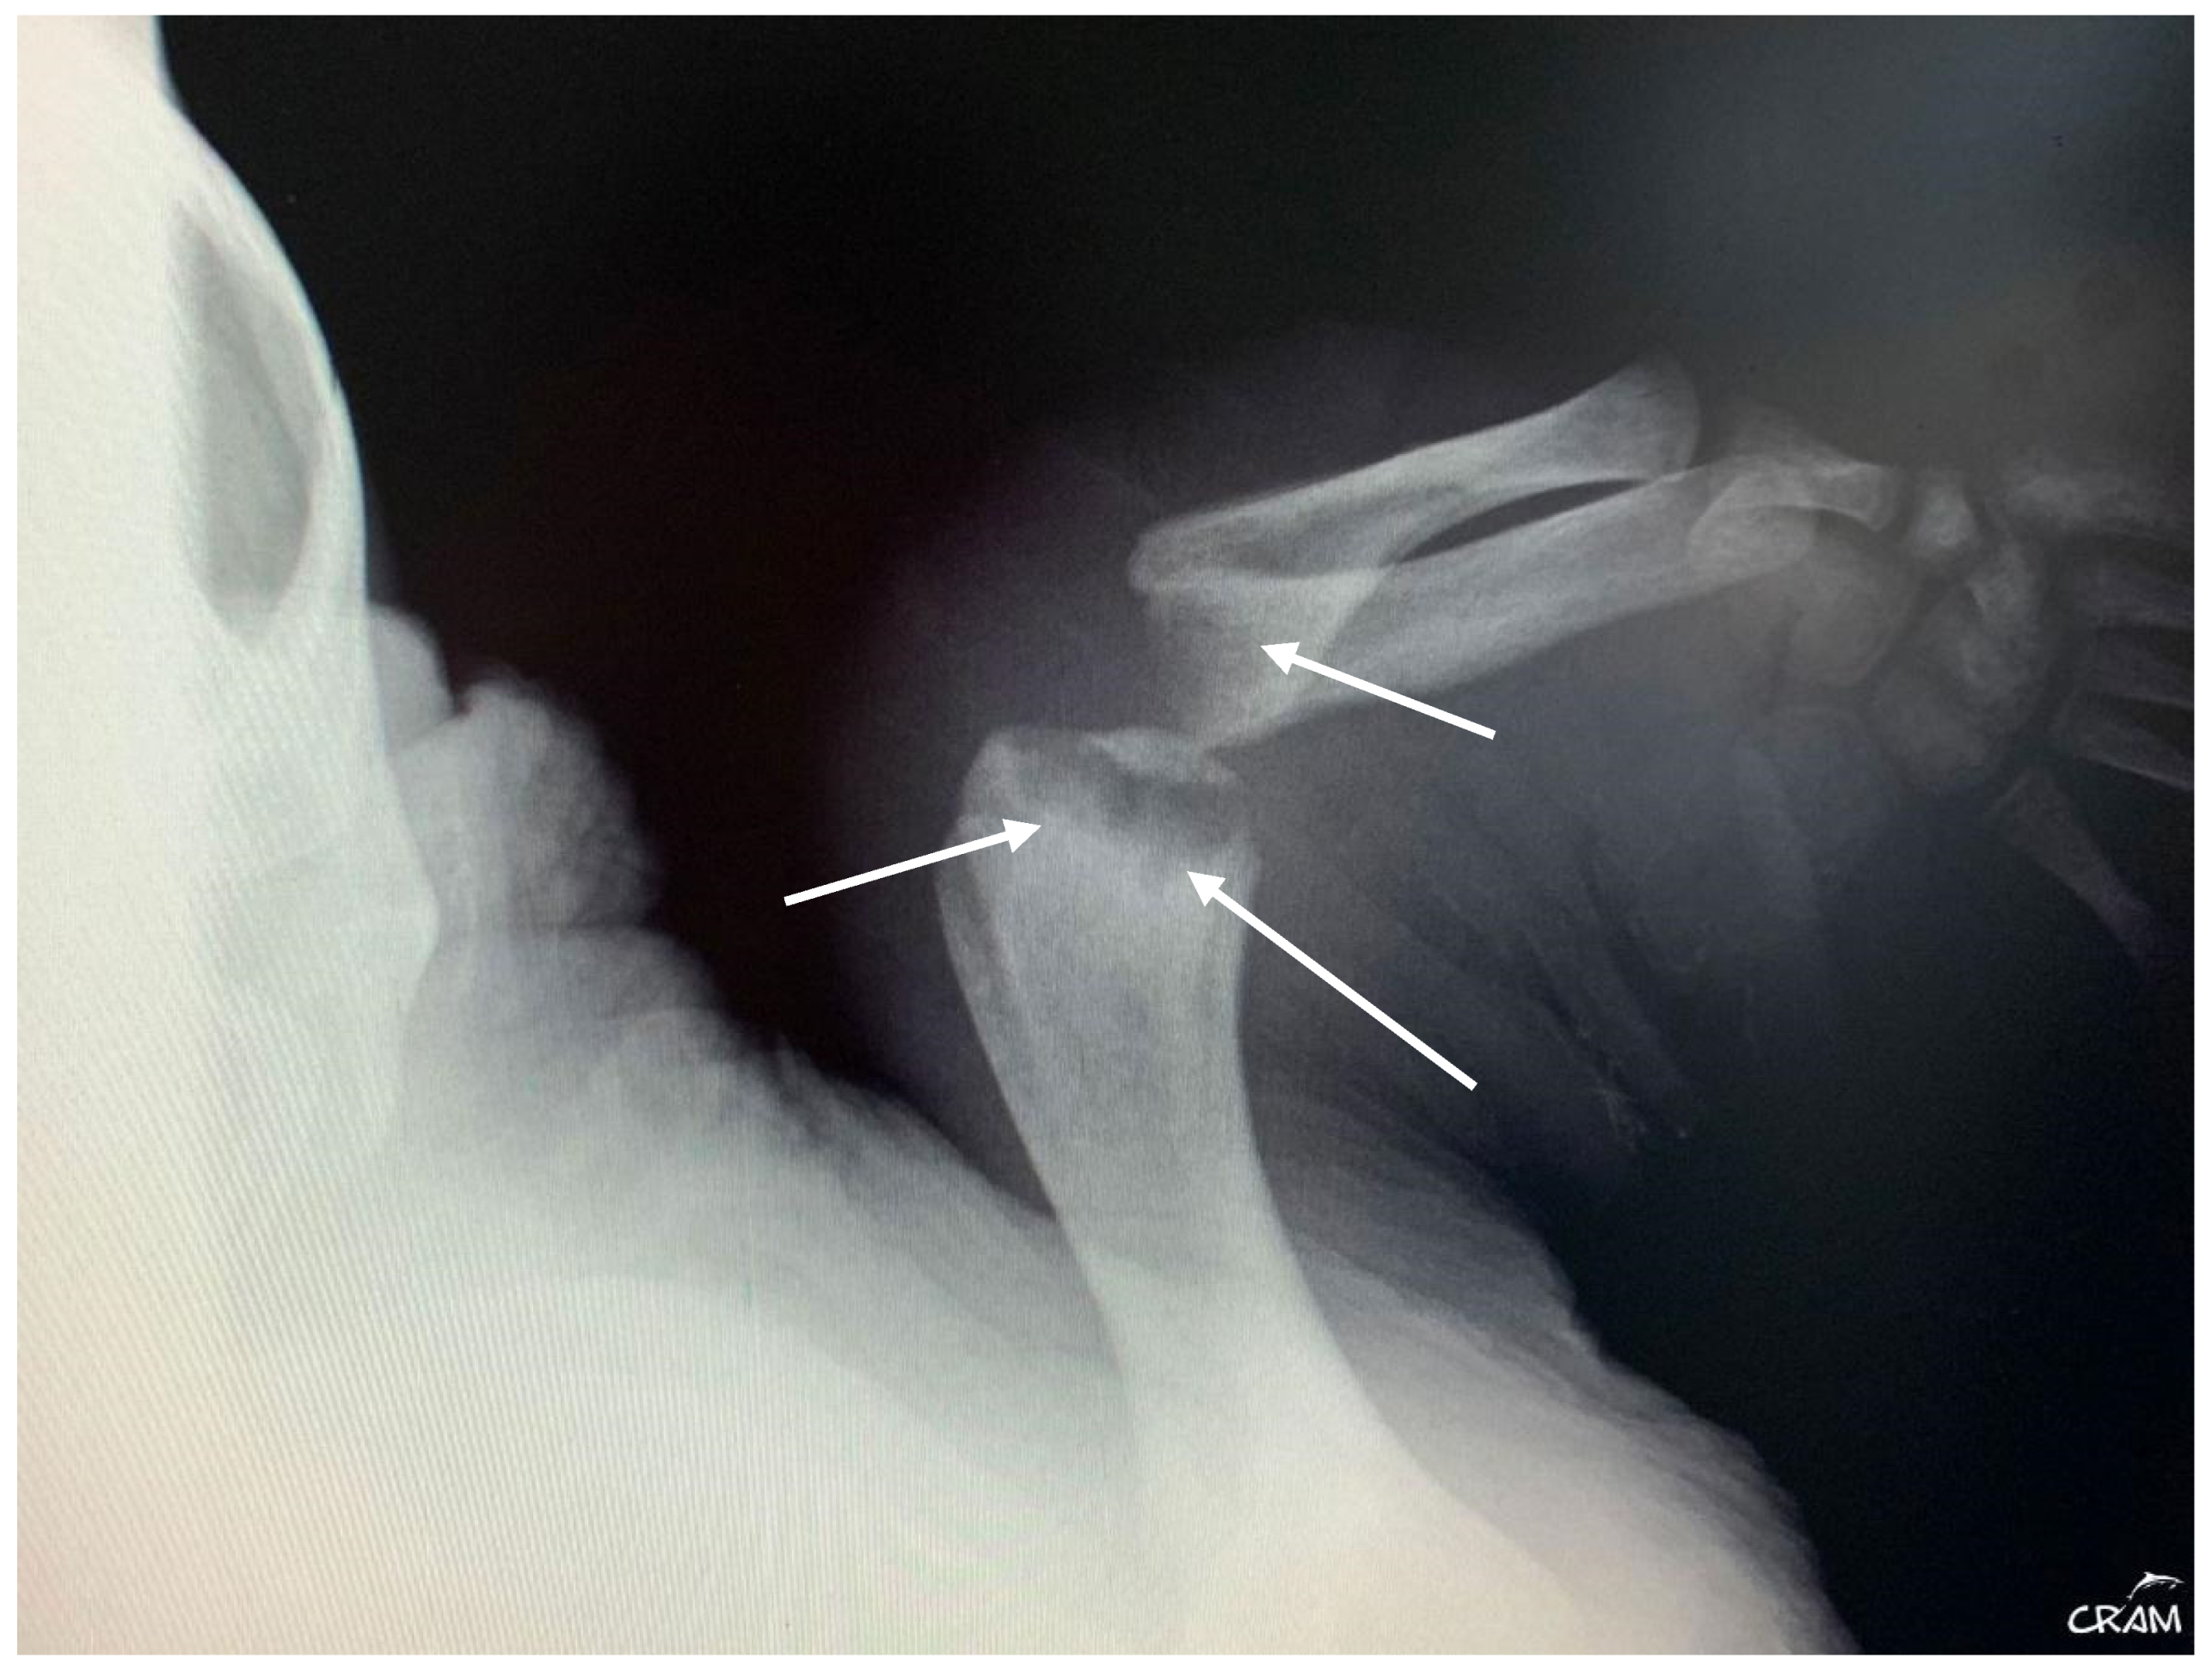

Hard edema with increased periarticular soft tissue and pain was noticed at palpation during clinical evaluation in veterinary medicine [21]. At the beginning of signs, radiographic lesions were polyostotic and poorly defined (Figure 5 and Figure 6).

Early-stage lesions at day 45 of rehabilitation were characterized by a purely osteolytic process restricted to the distal end of the humerus and femur and the proximal end of the radius, ulna, and tibia, including demineralization of the surrounding bones. Osteolytic lesions were restricted to the epiphysis and metaphysis of long bones, and no lesions were detected in the diaphysis.

Figure 5. Dorsoventral radiograph of the right front flipper at day 45 of rehabilitation. Well-defined bone lesions (arrows) are noted. Lesions are lytic with relevant osteopenia and no bone remodeling. The lytic process is seen communicating with the joint space in the elbow joint.

Figure 6. Right pelvic girdle in dorso-ventral view at day 45 of rehabilitation. Visible bone lysis on the distal end of the right femur (arrow).